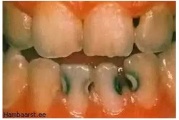

Hambaauguks ehk kaariesekahjustuseks nimetame hamba kõvakoe kahjustust, mille on põhjustanud hambapinnal elava mikroobiikihi ehk biofilmi elutegevuse jääkaine- piimhape. See hape söövitab hambakude ehk lahustab sellest välja mineraale, mille tagajärjel hambakude pehmeneb. Kahjustus tungib Loe edasi »

Sümptomid:

- hambas on auk (9)